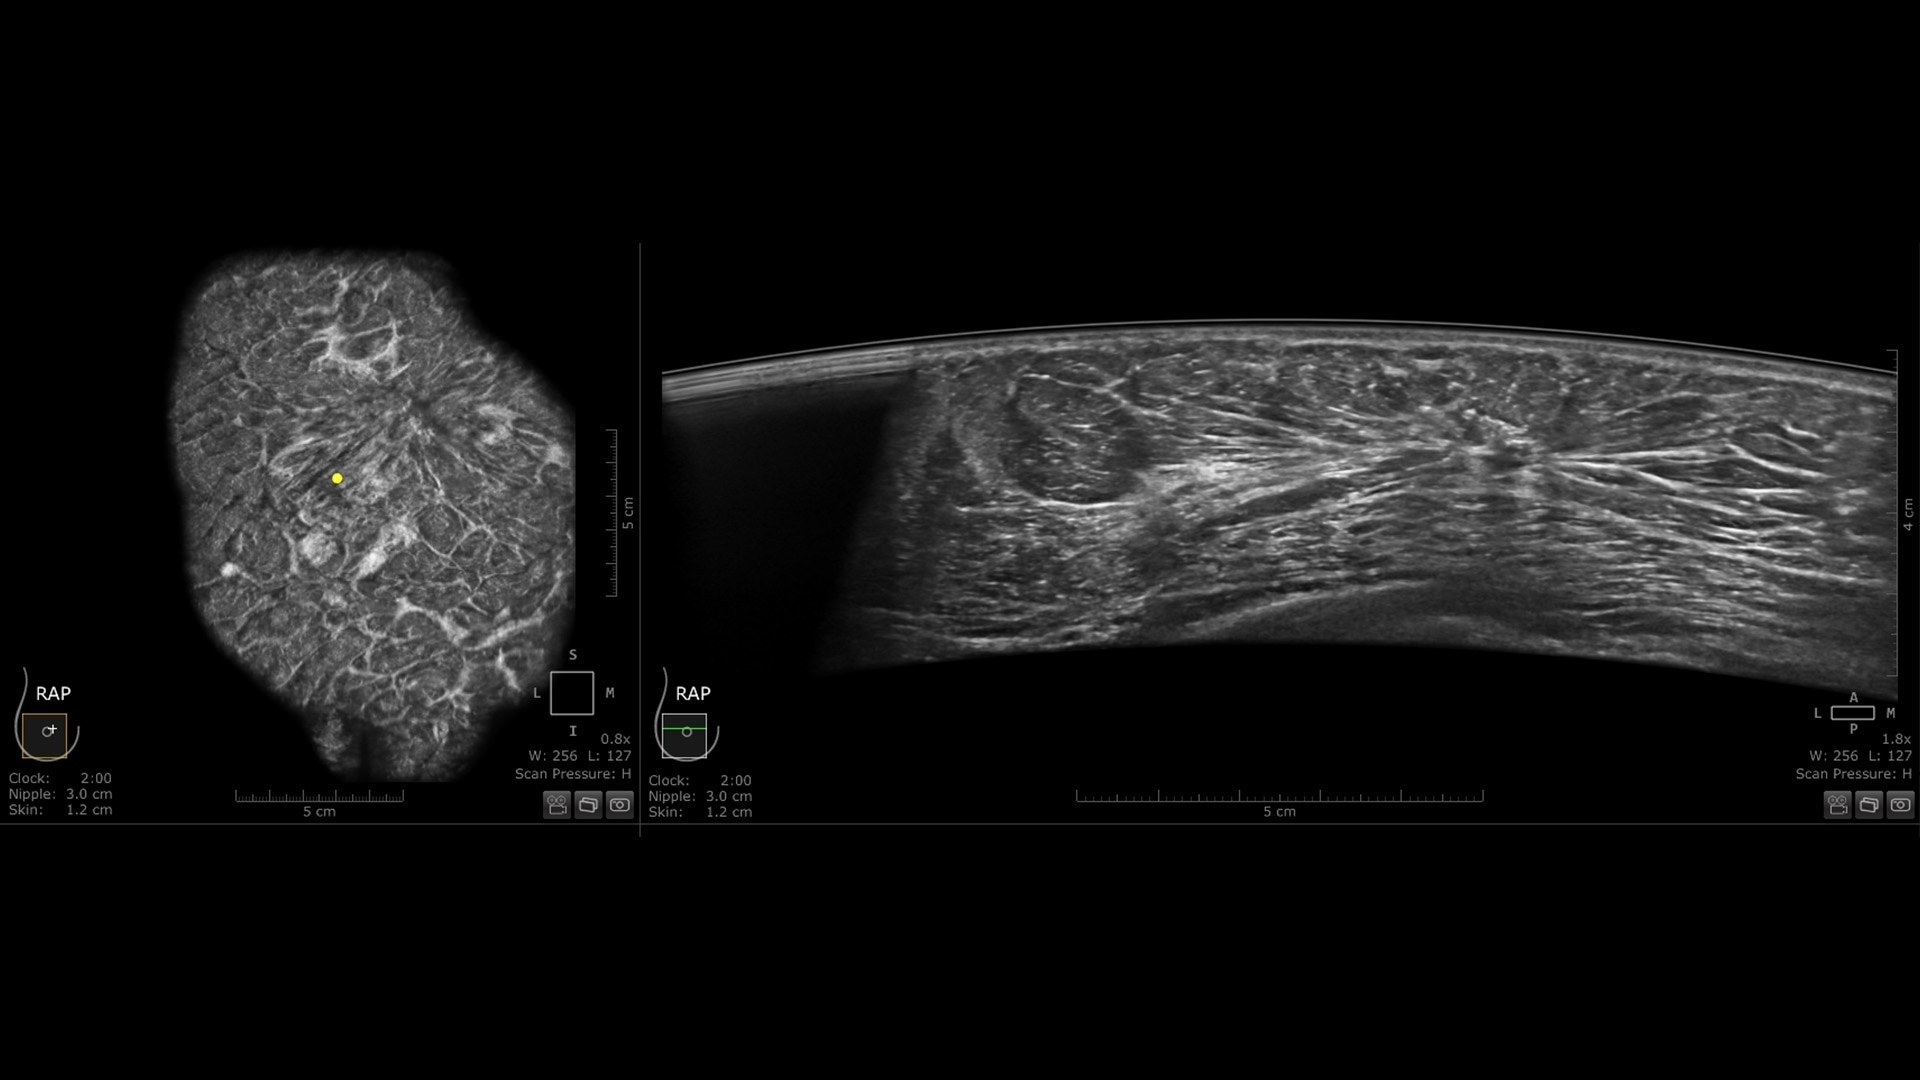

Productivity powered by AI

Boost clinical confidence and efficiency with AI-driven scanning and reading